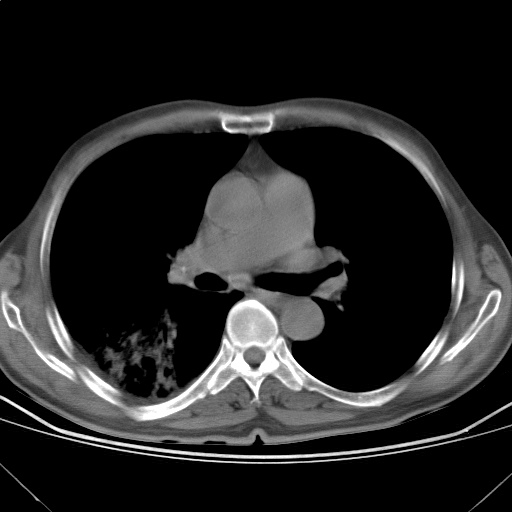

以下是引用随光逐影在2009-5-1 13:53:00的发言:[br]考虑为:1)两肺血行播散型肺结核;2)右肺下叶炎症感染。3)右侧胸膜增厚。